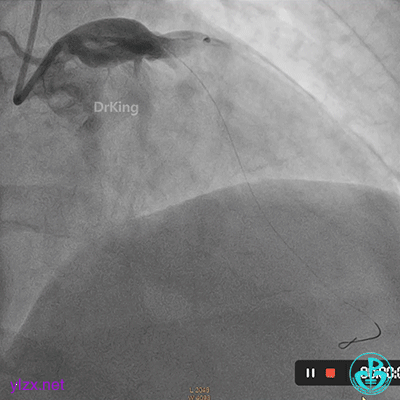

03 急诊冠脉造影

右冠脉粗大,近中段瘤样扩张明显,中段闭塞,局部可见大块血栓影。

首选开通右冠脉,导丝到达闭塞段远端,球囊扩张后,可见大量血栓,抽吸导管反复抽吸出大量血栓。冠脉内推注尿激酶原20mg,复查造影提示右冠脉远端显影,调整导丝至远段。

球囊再次扩张闭塞段,并对后降支及左室后支开口行对吻球囊扩张,复查造影示血流3级,无夹层行成,右冠脉远段仍可见血栓影。